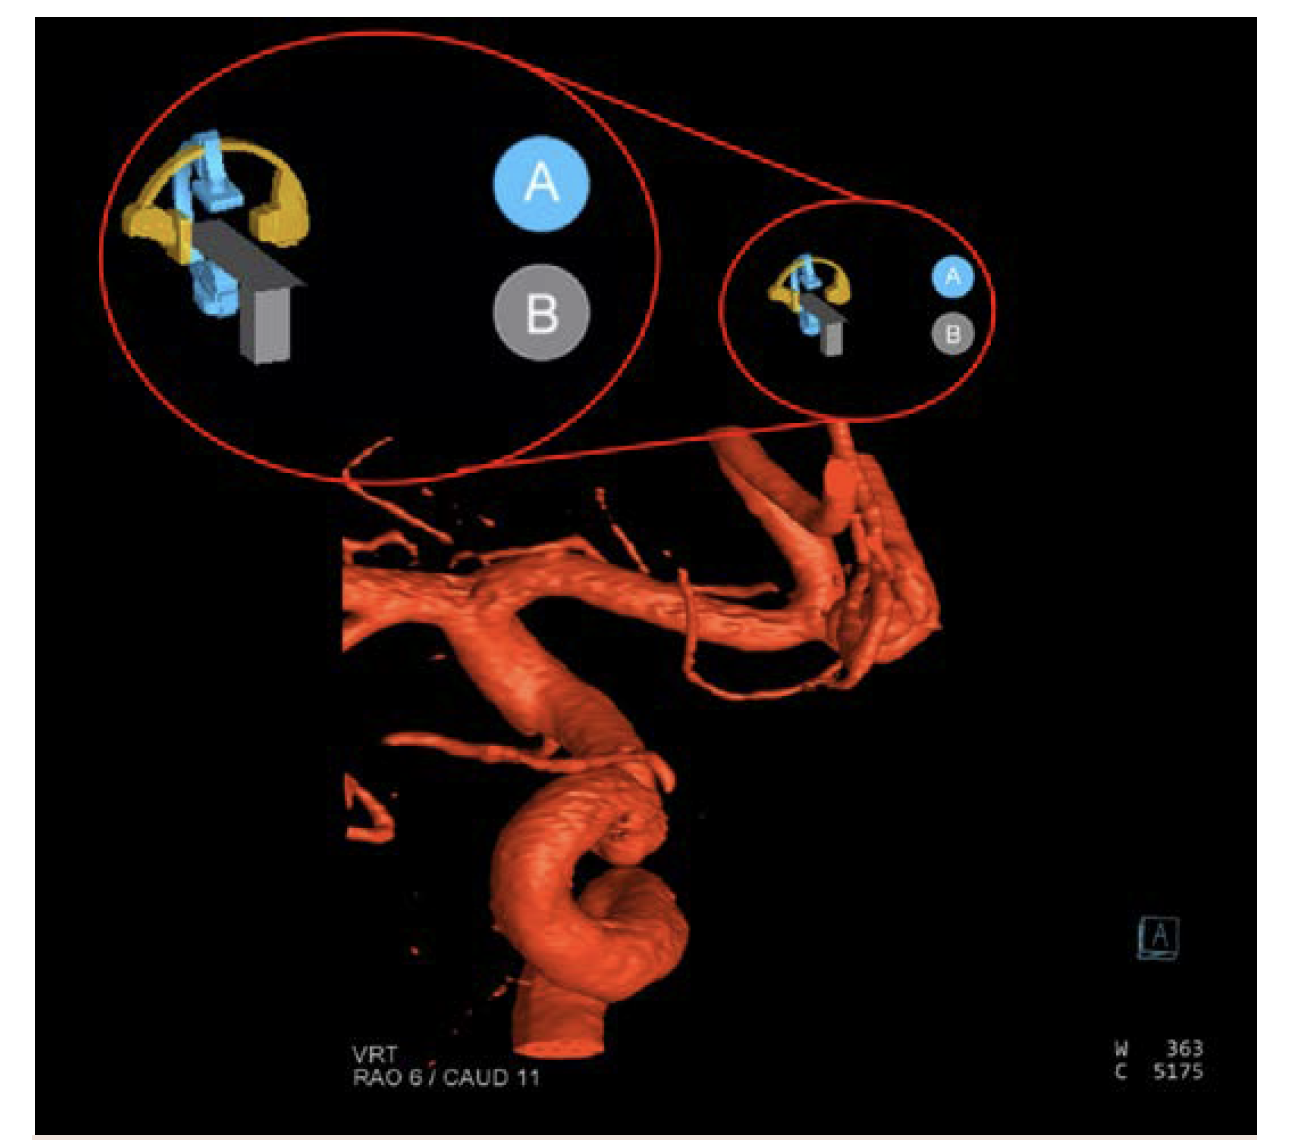

Imaging was performed with a 4-second DSA 3D acquisition with simultaneous injection in both vertebral arteries, power-injected on the left and hand-injected on the right (Figure 11). The plan based on these images was to flow divert from the left vertebral artery into the distal basilar artery and coil the distal right vertebral artery. Originally, the plan was to embolize the right vertebral artery distal to the posterior inferior cerebellar artery (PICA) origin. However, this plan changed based on findings from the right vertebral injection—findings that were dependent on the resolution of the imaging.

The aneurysm analysis tool was utilized to assess arterial diameters in both the distal and proximal landing zones as well to choose a stent length for the first stent and make an initial plan for the construct (Figure 12).